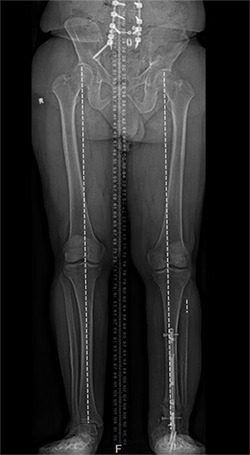

The operation took place in November 2022. Because Natale’s ankle was fused, Marecek chose to lengthen Natale’s tibia, or shin bone, rather than his femur. Marecek also identified that Natale’s ankle had been fused out of alignment. So, first he corrected the ankle’s alignment, then he broke Natale’s tibia and inserted a distraction rod—the kind that could push the two sides of the broken bone apart.

Natale could not put any weight on the leg for three months. After that the distraction rod was removed and replaced by a weight-bearing rod.

Natale says he had to do a lot of physical therapy, stretching the muscles to make space for the longer leg bone. It was about six months before Marecek gave him the go-ahead to put his full weight on it. Even after a year, X-rays showed the bone still hadn’t completely filled in the gap around the rod in his tibia.